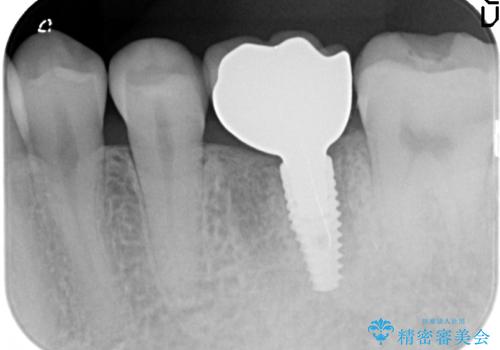

- 右上の銀歯を白くしたいといらっしゃった方の症例です。

右上4、5番目の歯はオールセラミッククラウンによる補綴、6番目の歯はセラミックインレーによる修復を行いました。